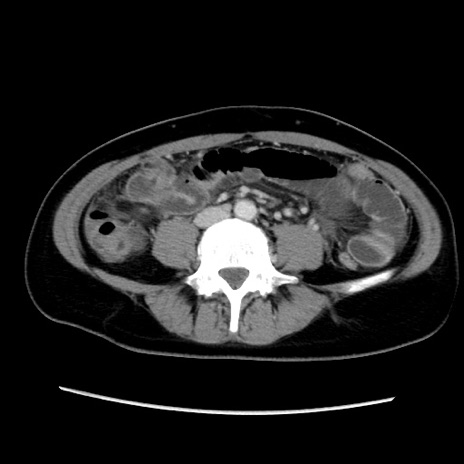

症例39(横断像)

【症例】40歳代女性

【主訴】上下腹部痛

【現病歴】2日目から下腹部痛あり。夜間は痛みで眠れなかった。昨日より上腹部痛と下痢が出現。臥位で痛みは軽快したため、休んでいた。本日になって臥位でも立位でも痛みが強くなってきたため救急要請。

【既往歴】子宮内膜症

【身体所見】部:平坦・軟、左上下腹部に圧痛あり、反跳痛あり。

【データ】WBC 21800、CRP 26.78